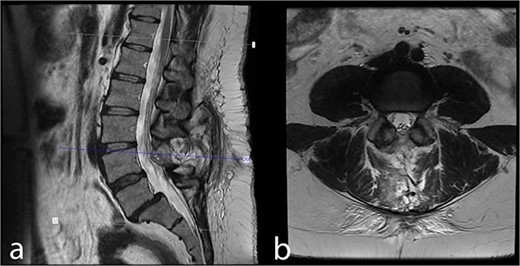

A 38-year-old female with a 1-month history of tailbone pain was admitted to the hospital. No significant medical history was present. On examination, all lower extremities were rated 5/5 for motor function. The senses and reflexes were symmetrical and intact. The patient did not report any problems with urinary or fecal continence. MRI revealed an intradural lesion at the L4 level (Fig. 1).

Preoperative MRI scans demonstrate a 17 × 12 × 15 mm intradural lesion posterior to the L3–4 disc and upper part of the L4 corpus. (a) The edge of the hypointense lesion is not so sharp in the midsagittal T2-weighted image. (b) In contrast to the sagittal T2-weighted image, the tumor appears to be hyperintense in the axial T2-weighted image. Because the nerve fibers are compressed by the tumor toward the dura CSF is not visible. (c) Midsagittal T1-weighted image shows a barely noticeable intradural tumor that is isointense with the vertebral body. (d) On midsagittal contrast-enhanced T1-weighted image, the tumor was homogeneously enhanced and became prominent.